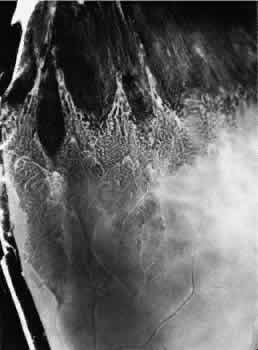

ZONULAR-TRACTION RETINAL TUFT

The zonular-traction retinal tuft always projects from the retinal surface internally and anteriorly toward the zonule (Fig. 40). Usually single and located within the vitreous base, zonular-traction retinal tufts are joined to zonular fibers at the apex; the tufts, which vary in length and thickness, are associated with a broad range of trophic and tractional alterations at the retinal end of the process. Histopathologic changes include zonular attachments at the apex, neuroglial cells within the tuft, and degeneration with retinal thinning at the base (Fig. 41). Retinal holes and tears result from the combination of trophic changes at the base and traction resulting from zonular fibers. Within the vitreous base and posterior to it, zonular-traction tufts may be associated with partial-thickness or full-thickness retinal tears that can occur in the absence of posterior vitreous detachment.

Fig. 40. Zonular-traction tuft of the peripheral retina. Tuft is drawn at an acute angle from the retinal surface toward the ciliary body and shows microcystic degeneration anteriorly. Posteriorly, the tuft splays; the retina at its base shows marked trophic change, including three full-thickness holes (arrow). (× 20.)

Fig. 41. Zonular-traction tuft (arrow) drawn at an acute angle from the retinal surface toward ciliary body with dense-staining glial cells along surface. Base of tuft is microcystic and has full-thickness trophic hole. (Hematoxylin-eosin; × 150.)

Zonular-traction tufts are present at birth and detected with equal frequency in patients of all ages; they are noted in 15% of patients, are bilateral in 15% of affected people, and thus are evident in 9% of all eyes (see Table 3). These tufts are most common in the nasal quadrants, usually attached to the retina less than 0.5 mm posterior to the ora serrata and only infrequently attached to the retina posterior to the vitreous base.27,36

Clinical examination of the peripheral fundus reveals zonular-traction tufts in patients of all ages. These lesions are distinguished from noncystic and cystic retinal tufts by their greater size, sharp anterior angulation, and close proximity to the ora serrata. Zonular-traction tufts are a significant cause of small, round retinal holes in the extreme periphery of the retina. Although retinal holes within the vitreous base are considerably less likely to produce retinal detachment than holes posterior to the vitreous base, surgical aphakia or pseudophakia, which necessarily involves some form of zonular traction, is associated with an increase in the frequency of retinal detachment, which is likely to be related to small retinal breaks in the nasal periphery.36,37